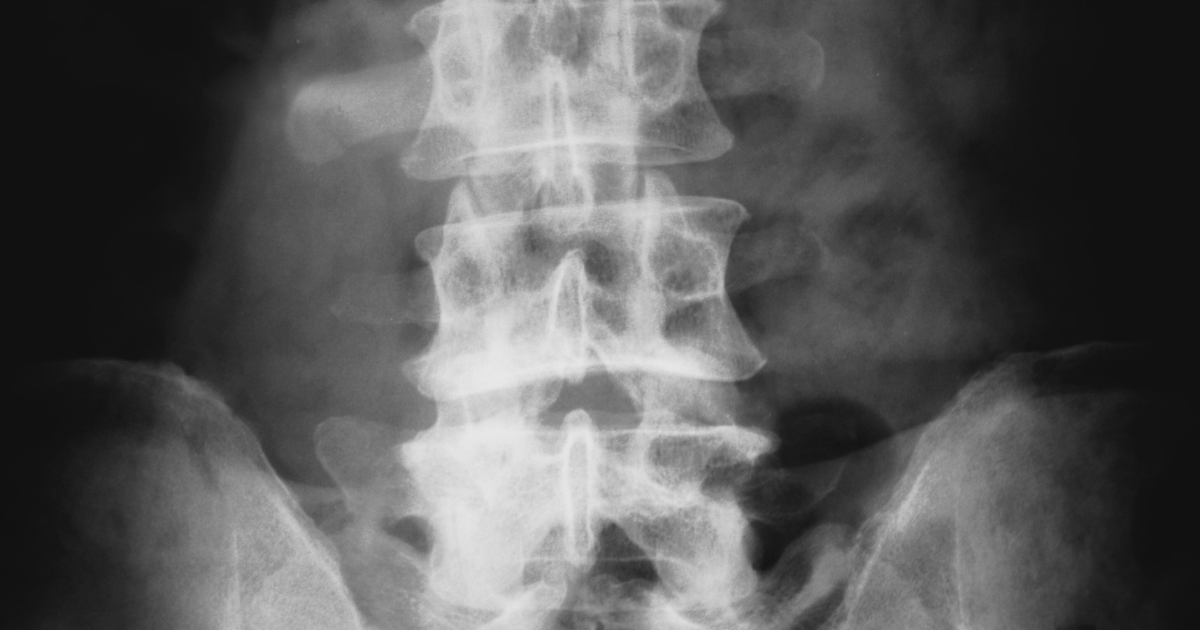

脊椎圧迫骨折による腰痛

骨粗鬆症の方に多い骨折です

尻もちをついた時や重いものを持った時など、日常生活のちょっとした動きで折れてしまいます。体を動かそうとするととても痛いのですが保存療法の場合はコルセットをつけて痛みに耐えるほかありません。

・レントゲン上では異常はない(骨折ではないなど)